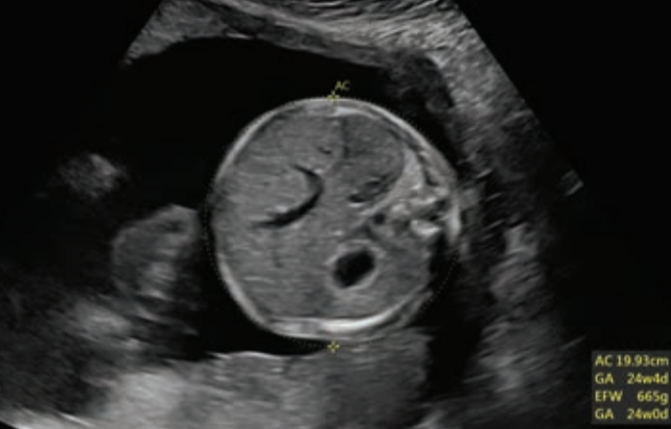

- Innovadora Arquitectura del Sistema Radiance para una calidad y precisión de imagen en 2D/3D/4D.

- Evaluar la salud fetal desde las etapas tempranas.